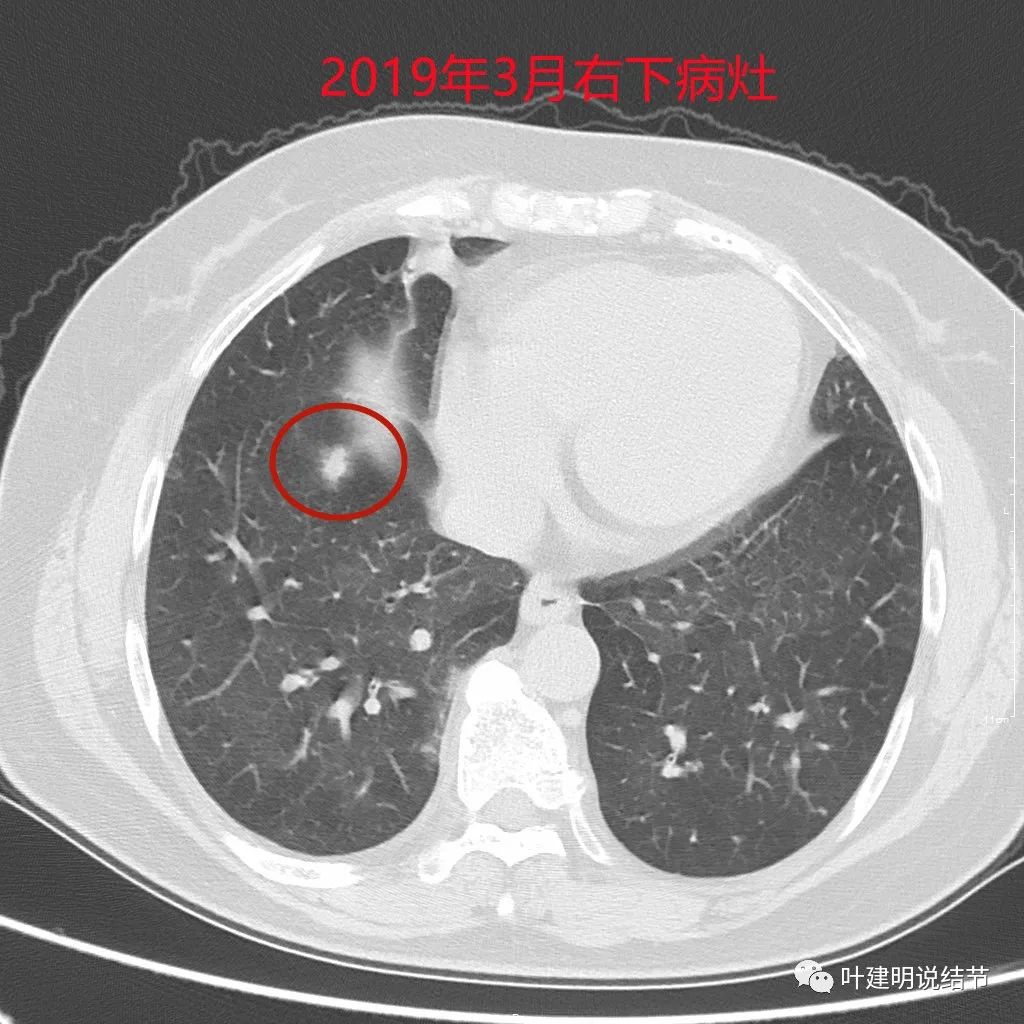

近日某A来复查,见右下叶结节较前有所增大进展。某A告诉我,2年多前已经告诉她右下结节也可能是恶性的,但特征还不够典型,需以后随访对比。另外即使恶性,也要拉长两肺手术的间隔才有可能切除,否则肺功能也无法耐受再次手术。这我倒真有些记不清当时具体的*法讲**了呢。我们先来比较下右下肺这结节每次复查时的对比:

前次手术时右下结节偏实性,不太致密,边缘显模糊,还不能认定为恶性,但需随访观察对比